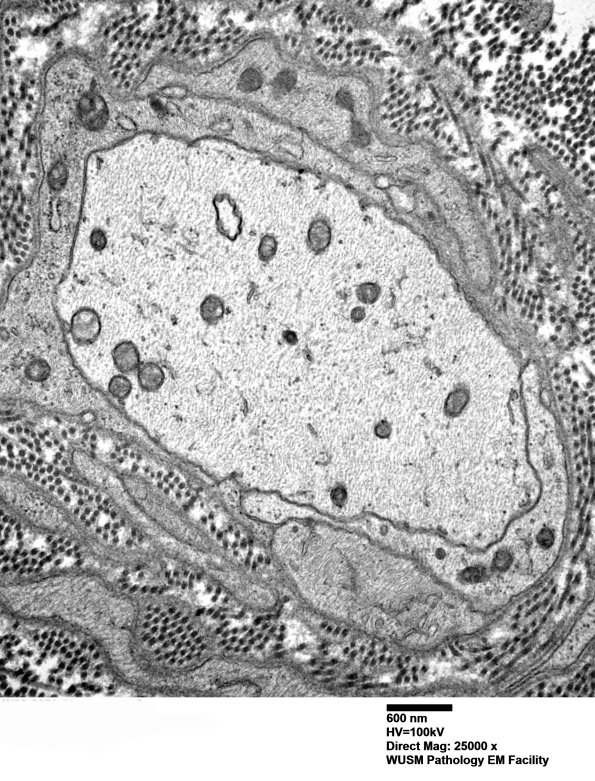

This demyelination is again accompanied by a prominent axonal cytoskeleton. Higher magnification of image #5B1. (electron micrograph)